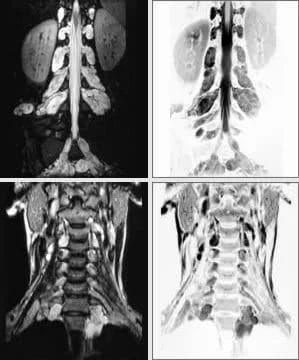

A patient presents with ‘café au lait’ spots and a subcutaneous mass in the abdomen.

High-resolution T2FSE images demonstrate multiple neurofibromas throughout the cervical and lumbar spine. There are also plexiform changes in the brachial plexus.